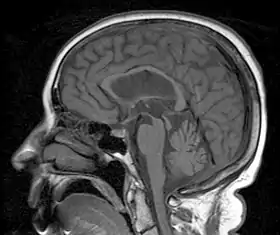

A person with progressive dementia, ataxia, and incontinence. A clinical diagnosis of normal-pressure hydrocephalus was entertained. Imaging did not support this, however, and on formal testing, abnormal nystagmus and eye movements were detected. A sagittal view of the CT/MRI scan shows atrophy of the midbrain, with preservation of the volume of the pons. This appearance has been called the "hummingbird sign" or "penguin sign". Also, atrophy of the tectum is seen, particularly the superior colliculi. These findings suggest the diagnosis of progressive supranuclear palsy.[1] | |

Magnetic resonance imaging (MRI) is often used to diagnose PSP. MRI may show atrophy in the midbrain with preservation of the pons giving a "hummingbird" sign.[27]